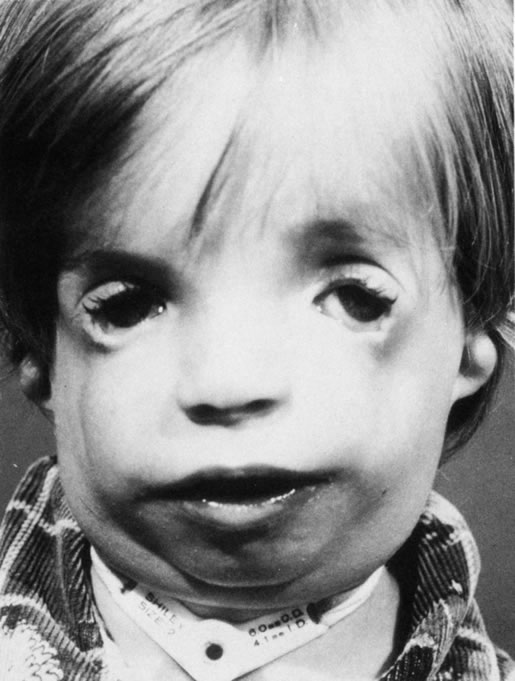

Anophthalmos and microphthalmos are usually unilateral and may be associated with a variety of craniofacial and systemic anomalies, including orbital hypoplasia, facial clefts, basal encephalocele, hemifacial microsomia, mandibulofacial dysostosis, cardiac anomalies, polydactyly, and mental retardation. When they occur unilaterally, they also can be associated with anomalies of the contralateral “normal” eye, including cataract, cornea1 opacities, microphthalmos, coloboma, epibulbar dermoids, and nystagmus. Anophthalmos and severe microphthalmos frequently are associated with contracted conjunctival fornices, phimotic eyelids, and generalized hypoplasia of the periocular soft tissues (Fig. 1). When soft tissue contractures occur, the early use of conformers is essential to expand these tissues.2 This treatment should be instituted in the first month of life, with progressive enlargement of the conformer over time to achieve maximum expansion of the conjunctival fornix. Unfortunately, this treatment usually does not stimulate adequate orbital bone growth, and unilateral microphthalmos and anophthalmos may be associated with secondary orbital hypoplasia (Fig. 2). Serial implantation of progressively larger orbital implants or placement of expansile orbital implants has been advocated to stimulate bony orbital development.3,4